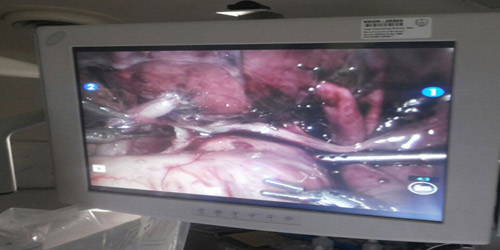

وحول مراحل العملية أشار الدكتور الحازمي الى انه تم ادخال كاميرا عالية الدقة و احدث الالات الجراحية عن طريق شقوق صغيرة لا تتجاوز 8 ملم دون الحاجة لشق جراحي كبير في البطن.

وأردف قائلا تم الاستعانة بروبوت يترجم حركات يد الجراح بدقة عالية، وتمت متابعة جميع تفاصيل العملية بكاميرا ثلاثية الابعاد عالية الوضوح.